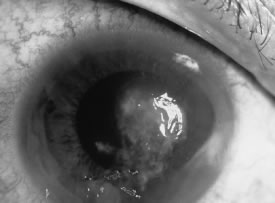

There is no distinguishing clinical sign by which to recognize the genus or species of the infectious filamentous fungus. F. solani is the most virulent organism and typically produces rapidly progressive infection characterized by epithelial and stromal ulceration, dense stromal necrosis, abundant cellular infiltrate, and edema in the adjacent stroma and hypopyon (Figs. 8 and 9). Delicate feathery components are transient. Individual hyphal fragments are rarely visualized. Infection by certain species of Aspergillus and Scedosporium (Figs. 10 and 11) resembles F. solani keratitis and progresses rapidly. Infection by less virulent organisms, such as Curvularia and Alternaria species, produces small, focal (less than 3-mm diameter) areas of nonnecrotizing stromal inflammation with delicate feathery borders (see Fig. 1 and Fig. 12). Macroscopic pigmentation may develop in keratitis caused by Alternaria, Curvularia, and other dematiaceous fungi (Fig. 13).4,11,14 The central component may progress to dense, opaque, gray-white suppuration in the deep stroma without enlargement in total area and may be accompanied by mild inflammation in the adjacent stroma. Iritis is minimal to moderate. Infection caused by other, relatively less virulent organisms resembles herpes simplex or noninfectious keratitis (Fig. 14).

Fig. 13. Curvularia keratitis in a 75-year-old man following sand injury. Note the macropigmentation in the area of the epithelial and stromal ulcer and surrounding, nonnecrotizing stromal keratitis.